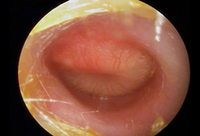

Otitis media with effusion

Otoscopy appearance of a bulging, erythematous tympanic membrane and absent landmarks

From the personal collection of Dr Armengol